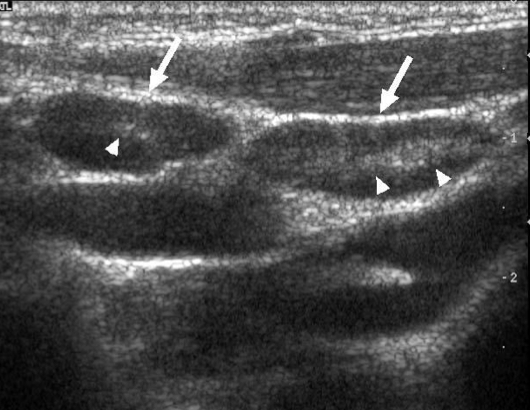

Normal